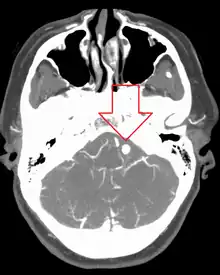

Diagnosis of a ruptured cerebral aneurysm is commonly made by finding signs of subarachnoid hemorrhage on a computed tomography (CT) scan. If the CT scan is negative but a ruptured aneurysm is still suspected based on clinical findings, a lumbar puncture can be performed to detect blood in the cerebrospinal fluid. Computed tomography angiography (CTA) is an alternative to traditional angiography and can be performed without the need for arterial catheterization. This test combines a regular CT scan with a contrast dye injected into a vein. Once the dye is injected into a vein, it travels to the cerebral arteries, and images are created using a CT scan. These images show exactly how blood flows into the brain arteries.